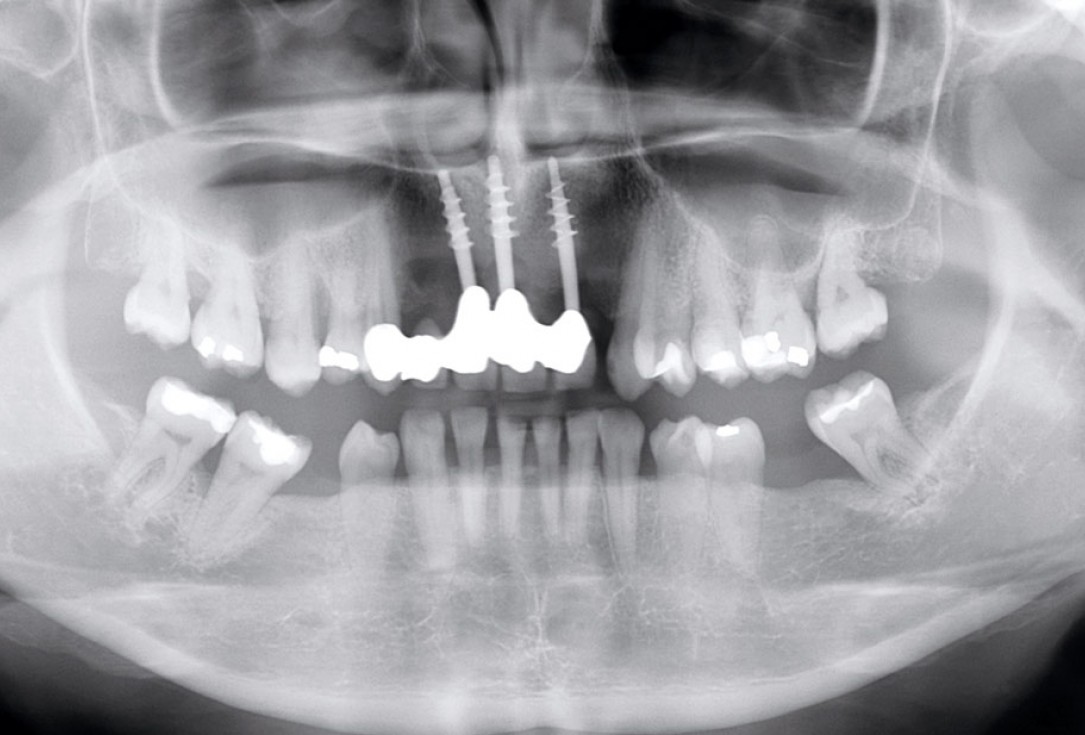

2/17 - Pre-operative x-ray scan: severe bone loss around three failing implantsRestoration of all four incisors with maxgraft® bonebuilder - Dr. Dr. Dr. O. Blume